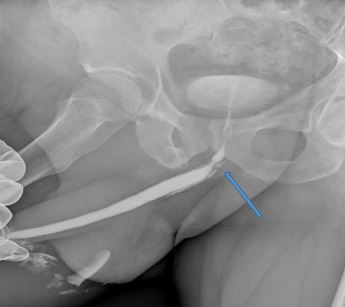

Когда мы регистрируем подобный график, проведя очень простое исследование – урофлоуметрию, мы для выяснения локализации и протяженности стриктуры уретры и определения степени сужения мочеиспускательного канала выполняем рентгеновское исследование – уретрографию. Вот так выглядела картинка уретрографии до операции (рисунок 2).

Рис. 2. Уретрография пациента до операции. Стриктура уретры показана стрелкой

Это исследование представляет собой рентгеновский снимок мочеиспускательного канала, в который вводят жидкий рентгеновский контраст. Мы видим значительное рубцовое сужение мочеиспускательного канала, которое, судя по рассказу пациента, было связано с перенесенной несколько лет назад мочеполовой инфекцией. Пациента несколько раз лечили от мнимого «простатита», а диагноз стриктуры уретры был установлен нами впервые. Какого-либо дополнительного обследования пациенту не требовалось, ему сразу было предложено оперативное лечение (реконструктивная хирургическая операция) в объеме анастомотической пластики уретры.